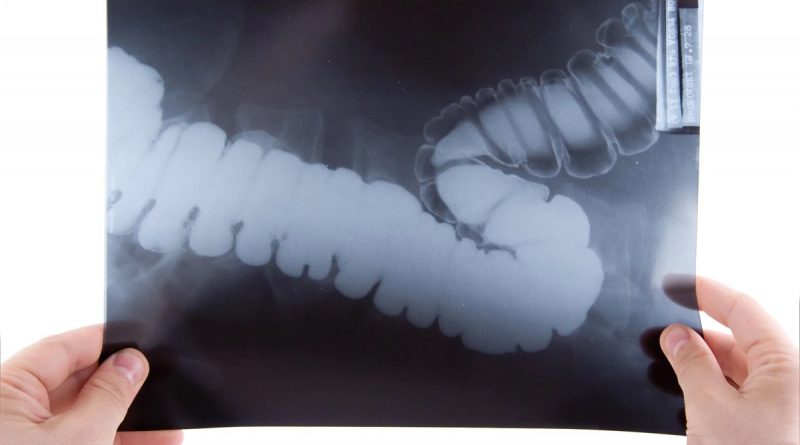

El cáncer colorrectal (CCR) se desarrolla en el colon y el recto (intestino grueso). En más del 80% de los casos, se genera primero un pólipo (crecimiento anormal de las células) denominado adenoma, que puede crecer lentamente durante más de 10 años y transformarse en cáncer si no se detecta y extirpa a tiempo.